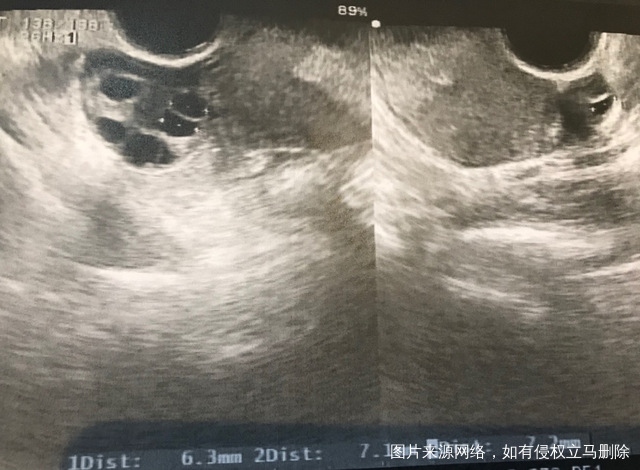

月经第四天查窦卵泡数,请看看图是否正常?左侧只有1个,右侧5个正常吗?监测排卵半年只有右侧排卵,左侧子宫和卵巢间有粘连,左侧卵巢什么问题导致不排卵?另外说我窦卵泡数比前几个月多了,这是好还是不好?